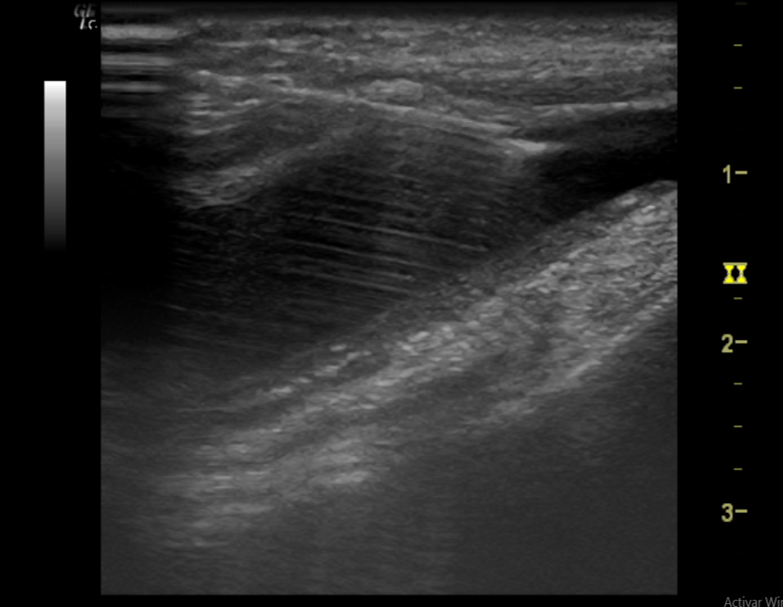

Descripción de los hallazgos ecográficos y las imágenes más relevantes para la resolución del caso

Enfermedad actual: Acude al Centro de Salud tras caída en una escalera y traumatismo en rodilla derecha. Gonalgia, EVA 8/10, impotencia funcional e importante inflamación que le impide caminar.

Exploración física: rodilla derecha muy inflamada, enrojecida y CON aumento de temperatura. Rebote (+). Dolor a la mínima flexión que impide su correcta exploración.

Pruebas complementarias: se realiza ecografía a pie de cama en la consulta de Atención Primaria.

Sinovitis de rodilla, derrame suprapatelar y posible hemartros postraumático.